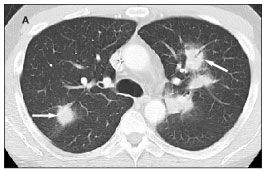

A chest radiograph showed bilateral nodular densities (Figure 1), and a chest CT scan also demonstrated a nodular pneumonia (Figure 2). Because of a high suspicion for a fungal infection, the patient was empirically treated with voriconazole with cefepime added for bacterial coverage. He underwent bronchoscopy with bronchoalveolar lavage (BAL) on hospital day 3; viral cultures were initially positive for only cytomegalovirus (CMV). All other cultures, including fungal, bacterial, and mycobacterial cultures; acid-fast bacilli smear; direct fluorescent antibody testing for P jiroveci and Legionella; and BAL cytology yielded negative results. Multiple blood cultures were also negative, but his serum CMV DNA level, detected by polymerase chain reaction (PCR) assay, was 77,900 copies/mL.

Figure 2.Chest CT scans showing multiple areas of airspace

consolidation (arrows) within the lungs with peripheral area of ground-glass opacity. A: Bilateral upper lobe consolidation. B: Right lower lobe pleural-based consolidation. C: Right lower lobe consolidation.